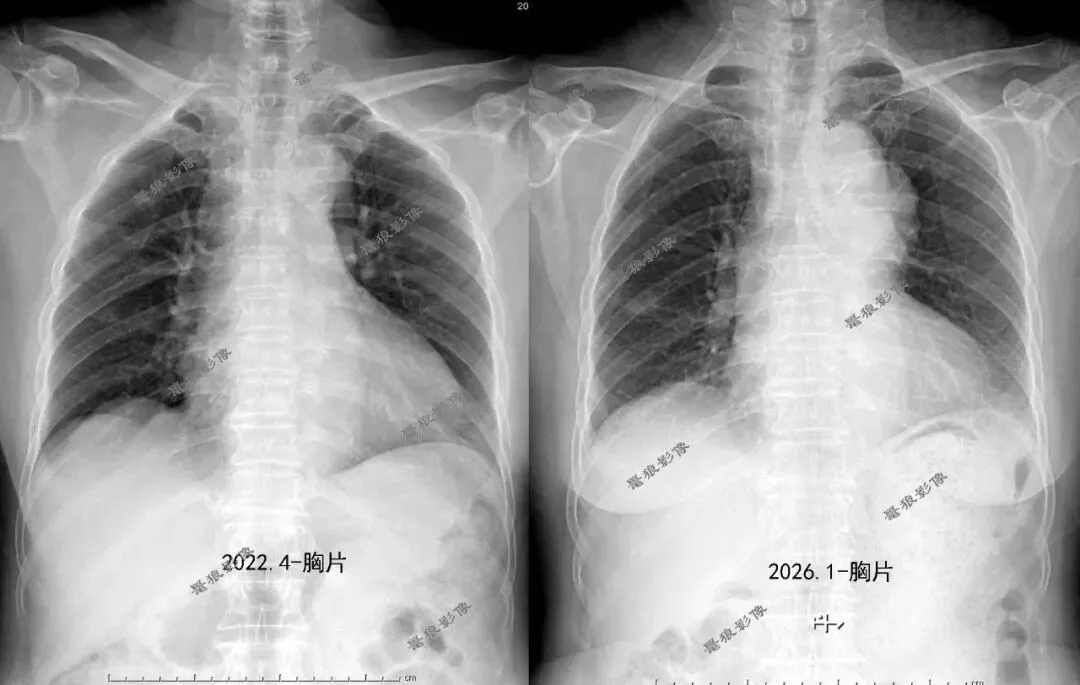

F  75y,颈痛入院。

一、入院常规胸片提示:

与前片2022年4月对比,新增主动脉弓旁瘤样软组织密度影,考虑主动脉瘤可能性大,请密切结合临床,建议进一步检查。